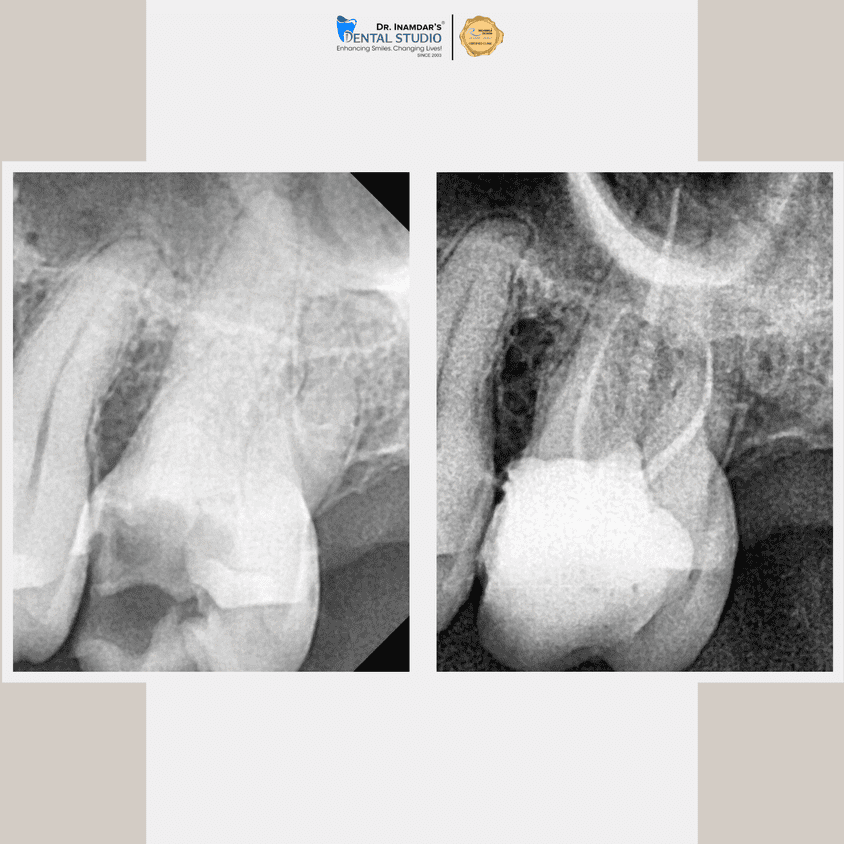

We begin with a detailed dental examination and digital X-rays to identify the source of infection.

The infected tissue is gently removed, and the tooth is thoroughly cleaned and disinfected.

The tooth is sealed and usually protected with a crown to restore strength and function.